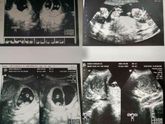

2 скрининг

13 февраля 2017 15:50

Сходили мы на второй скрининг✨.Врачиха сказала 100% мальчишка. Писюльку показала.Вообщем ждем сыночка ?Была уверенна, что будет девочка ?, но оказалось что ошибалась.